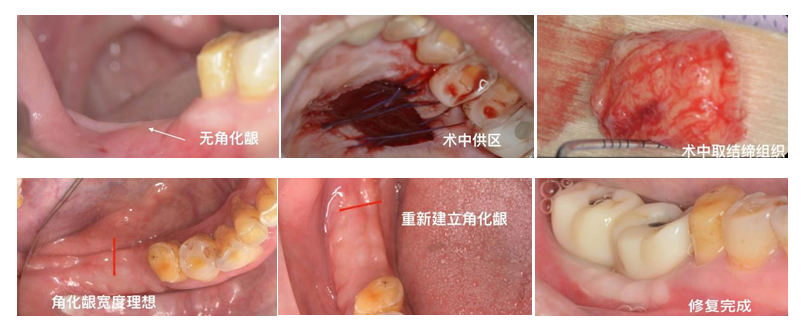

软组织移植技术:从口腔内的其他部位(如腭部)切取游离的牙龈组织,移植到需要增加牙龈厚度或宽度的部位,以改善牙龈的形态和功能。